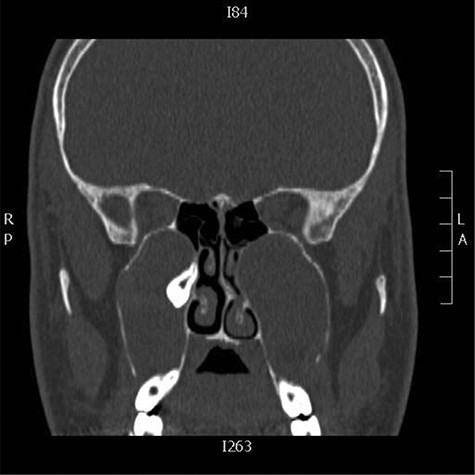

Clinical examination was unremarkable except for a septal spure to the left side for which paranasal sinus computed tomography (CT) scan was done (Fig. 1).

Coronal CT images showing bilateral cystic lesions in the maxillary antra with expansion and remodeling of the roof, lateral and medial walls, the right cystic lesion displaces ectopic tooth superiorly and medially in the region of the expanded remodeled ostiomeatal complex